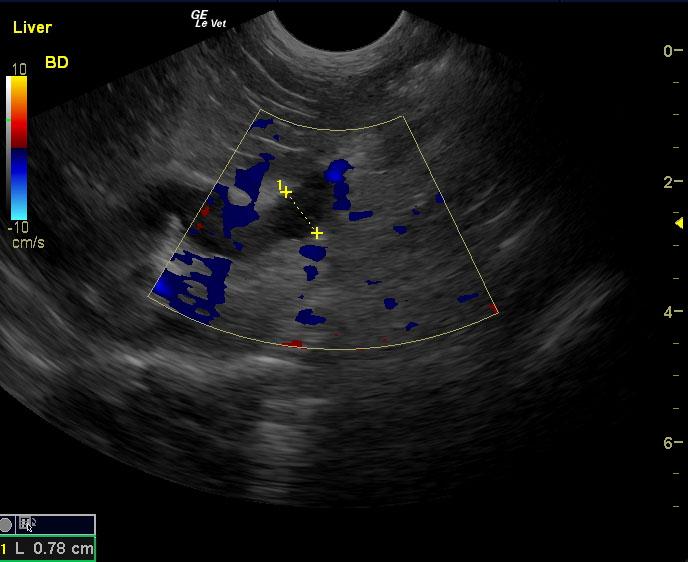

A 10-year-old, SF DSH cat was presented for acute onset vomiting and dehydration. Abnormalities on physical examination were icterus and dehydration. Pyuria with low urine SG was present on urinalysis. Urine culture was negative for bacterial growth after 24hrs. CBC and serum biochemistry showed marked leukocytosis with left shift and azotemia. Diffuse intestinal ileus was evident on survey radiographs.